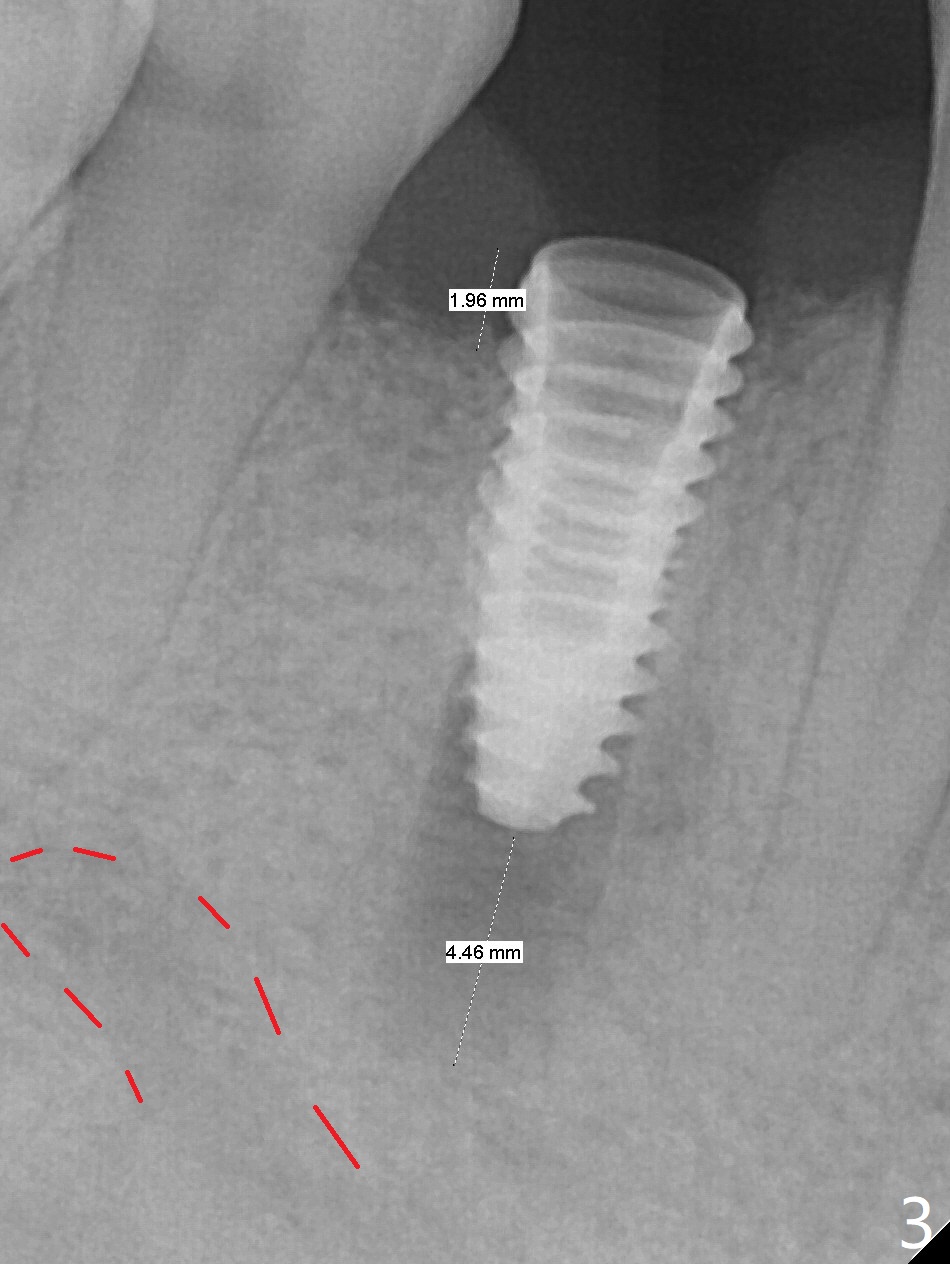

Immediately post extraction and curettage of the large buccal apical lesion, osteotomy is established in the lingual wall of the socket of #28 (slightly distal) for 17 mm vs. 15 mm socket depth (Fig.1 (red line: Mental Loop)). Following sequential osteotomy until 3.5x17 mm drill, a 4x10 mm dummy implant is partially placed with stability (Fig.2,3 (root measurement: mesiodistal 4 mm; buccolingual 7 mm)). A final implant (4x11.5 mm) is placed with insertion torque of 60 Ncm (Fig.4,5). Since the buccal crest is lower with the buccal gingival recession, the implant is intentionally placed deep as well as lingually so that autogenous bone and Vera graft mixture will be placed in the buccal gap (Fig.6 * (gauze at the moment)). The apical lesion decreases 4.5 months postop (Fig.7). Immediate implant and immediate provisional keep the papillae (Fig.8 *), but cannot prevent the buccal plate from atrophy (Fig.9 *). It appears that socket shield is able to accomplish the latter. The bone density next to the coronal threads increases 10 months post cementation (Fig.10 *) and seems to have continued to do so 1 year 4 months post cementation (Fig.11).